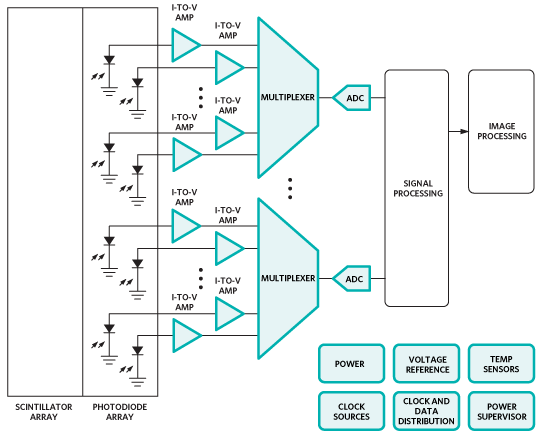

The x-rays pass through the body and strike a crystal scintillator, which absorbs the x-ray photons and re-emits visible-light photons that are captured in a photodiode array, creating an electrical signal. The current in the diode is proportional to the impinging light, and that current is either integrated or converted to a voltage in a transimpedance amplifier (TIA).

These signals are multiplexed via FETs to the analog-to-digital converters (ADCs), after which the signal may travel a fair distance to be processed and displayed (see Figure 2). If the ADCs are fast enough they can process more signals in the interval between exposures (on the order of hundreds of microseconds or greater), meaning one can do more multiplexing and use fewer converters, helping keep size and power down. The converters must also be able to handle the high dynamic range that is typical of the detected signal. Among the ADCs that Maxim recommends are the MAX11047/8/9 (16 bits) and MAX11057/8/9 (14 bits), having 4, 6, or 8 independent channels each. They can operate at up to 250 ksps.

Figure 2: A typical CT front end (Courtesy of Maxim).